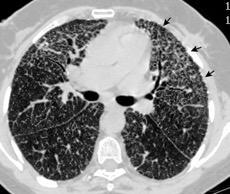

Microlitiasis alveolar con cambios “quísticos” subpleurales En ocasiones aparece como una capa de densidad grasa.

Línea negra visible en la periferia de los pulmones, entre la caja torácica y el pulmón. En TCAR parece existir una capa sutil quística en el espacio subpleural.

Felson B. The Roentgen diagnosis of disseminated pulmonary alveolar diseases. Semin Roentgenol 1967; Kosciuk P et al. Pulmonary alveolar microlithiasis. Eur Respir Rev 2020